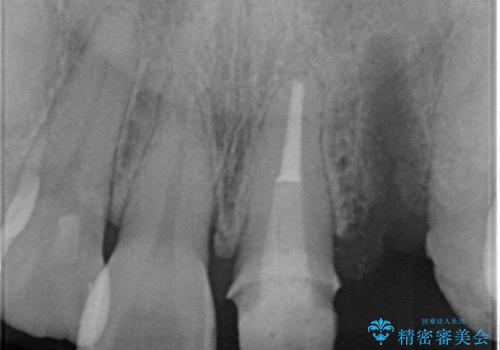

X線撮影や歯周組織検査から、クラウン下の虫歯の再発や歯の破折が疑われる状況でした。

左上2は、クラウン メタルコアの除去を行ったところ虫歯の再発や亀裂を認め、長期的な予後の期待が難しいことから抜歯を行い

ブリッジで審美性の回復を行っていく運びとなりました。